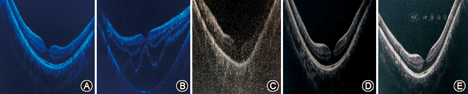

患者男性(弟弟),16岁。因左眼视力下降6个月,于2018年9月29日就诊于天津医科大学眼科医院。患者哥哥、母亲及舅舅均为马方综合征患者。全身体检:身高为2.05 m,瘦高体型,蜘蛛状指(趾),胸廓形态正常,心前区无隆起;超声心动图:主动脉根部相对扩张,二尖瓣松软、膨隆并少量反流,主动脉瓣反流(少量)。眼部检查:右眼裸眼视力为0.5,矫正视力为0.8(+5.50 DS-2.75 DC×15°);左眼裸眼视力为0.12,矫正视力为0.2(+6.00 DS-2.50 DC×165°);眼压右眼为12.6 mmHg(1 mmHg=0.133 kPa),左眼为10.1 mmHg;眼轴长度右眼为30.50 mm,左眼为30.36 mm;双眼外眼无异常,角膜透明,前房深度正常,右眼晶状体向上方脱位,左眼晶状体向鼻上方脱位(图1中A和B);双眼豹纹状眼底(图2中A和B)。角膜地形图(Pentacam三维眼前节分析仪):双眼角膜曲率较平,前表面曲率均为40.2 D(图3中A和B)。相干光层析成像术(optical coherence tomography,OCT)检查:右眼黄斑中心凹反射曲线存在,左眼视网膜劈裂,神经上皮层脱离(图4中A和B)。临床诊断:马方综合征;双眼晶状体半脱位;双眼高度近视眼视网膜病变;左眼视网膜劈裂。入院行左眼后巩膜加固术,术后左眼OCT示视网膜基本复位(图4中C)。眼部生物学参数见表1。

患者哥哥,16岁。因双眼视力下降6个月,于2018年9月29日就诊于天津医科大学眼科医院。全身体检:身高为2.05 m,瘦高体型,蜘蛛状指(趾),胸廓形态正常,心前区无隆起;超声心动图:主动脉根部扩张,二尖瓣松软、膨隆并少量反流,主动脉瓣反流(少量);左心室增大。眼部检查:右眼裸眼视力为0.5,矫正视力为0.9(+5.75 DS -2.50 DC×10°);左眼裸眼视力为0.5,矫正视力为0.9(+6.00 DS-2.50 DC ×170°);眼压右眼为9.8 mmHg,左眼为11.0 mmHg;眼轴长度右眼为30.12 mm,左眼为29.53 mm。双眼外眼无异常,角膜透明,前房深度正常,右眼晶状体向上方脱位,左眼晶状体向颞上方脱位(图1中C和D);双眼豹纹状眼底(图2中C和D)。角膜地形图(Pentacam三维眼前节分析仪):双眼角膜曲率较平,前表面曲率右眼为40.8 D,左眼为40.6 D(图3中C和D)。OCT检查未见异常(图4中D和E)。临床诊断:马方综合征;双眼晶状体半脱位;双眼高度近视眼视网膜病变。眼部生物学参数见表1。